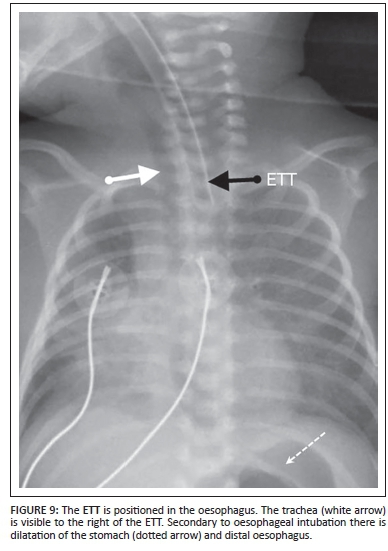

Endotracheal tube (ETT)

Uses: The ETT is inserted for ventilatory support and it also prevents aspiration. The ETT should be placed halfway between the thoracic inlet and the carina or 1.5 vertebral bodies above the carina.6

Complications

The most common complication is selective intubation of the bronchus (Figure 8a and Figure 8b). This results in collapse/ atelectasis of the contralateral lung. If the patient is on a ventilator, the ipsilateral lung can become hyperinflated, leading to pneumothorax or tension pneumothorax. Another serious complication is inadvertent oesophageal intubation (Figure 9).1 This complication is mostly diagnosed clinically and can be detected radiographically by an air-filled esophagus, over distended stomach and no ETT in the trachea. There are also other complications related to long-term intubation.